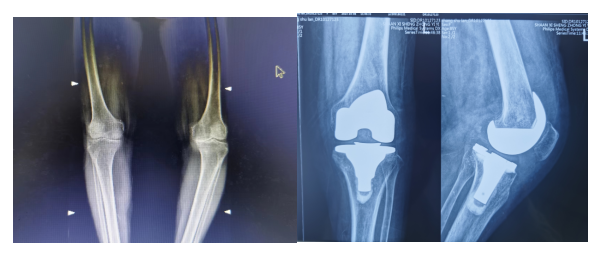

近日,省中医医院骨伤二科收治一位85岁高龄女性膝关节骨性关节病患者,因膝关节内翻畸形,疼痛明显,行走受限入住我科,本该是尽享天伦的年纪,她却时常被膝关节疼痛困扰,多次于外院保守治疗,效果不佳;最近几年越发严重,寝食难安。在邻居的介绍下,慕名来骨伤二科看诊,入院后全健主任医师、王彦鹏副主任医师团队详细查体阅片后,考虑患者疼痛明显,对日常生活影响大,保守治疗无明显缓解,有膝关节置换手术指征。考虑到患者85岁高龄,手术风险大,术后康复困难;随即组织科室专家团队充分讨论,围绕患者围手术期,在传统西医手术技术的基础上,不断融入创新,运用个性化治疗方案+中医特色治疗,力求有效优化、精准化治疗,结合科室特色,为患者制定了详细的手术及中西医结合康复计划,使患者安全手术,快速康复后出院。

术前术后